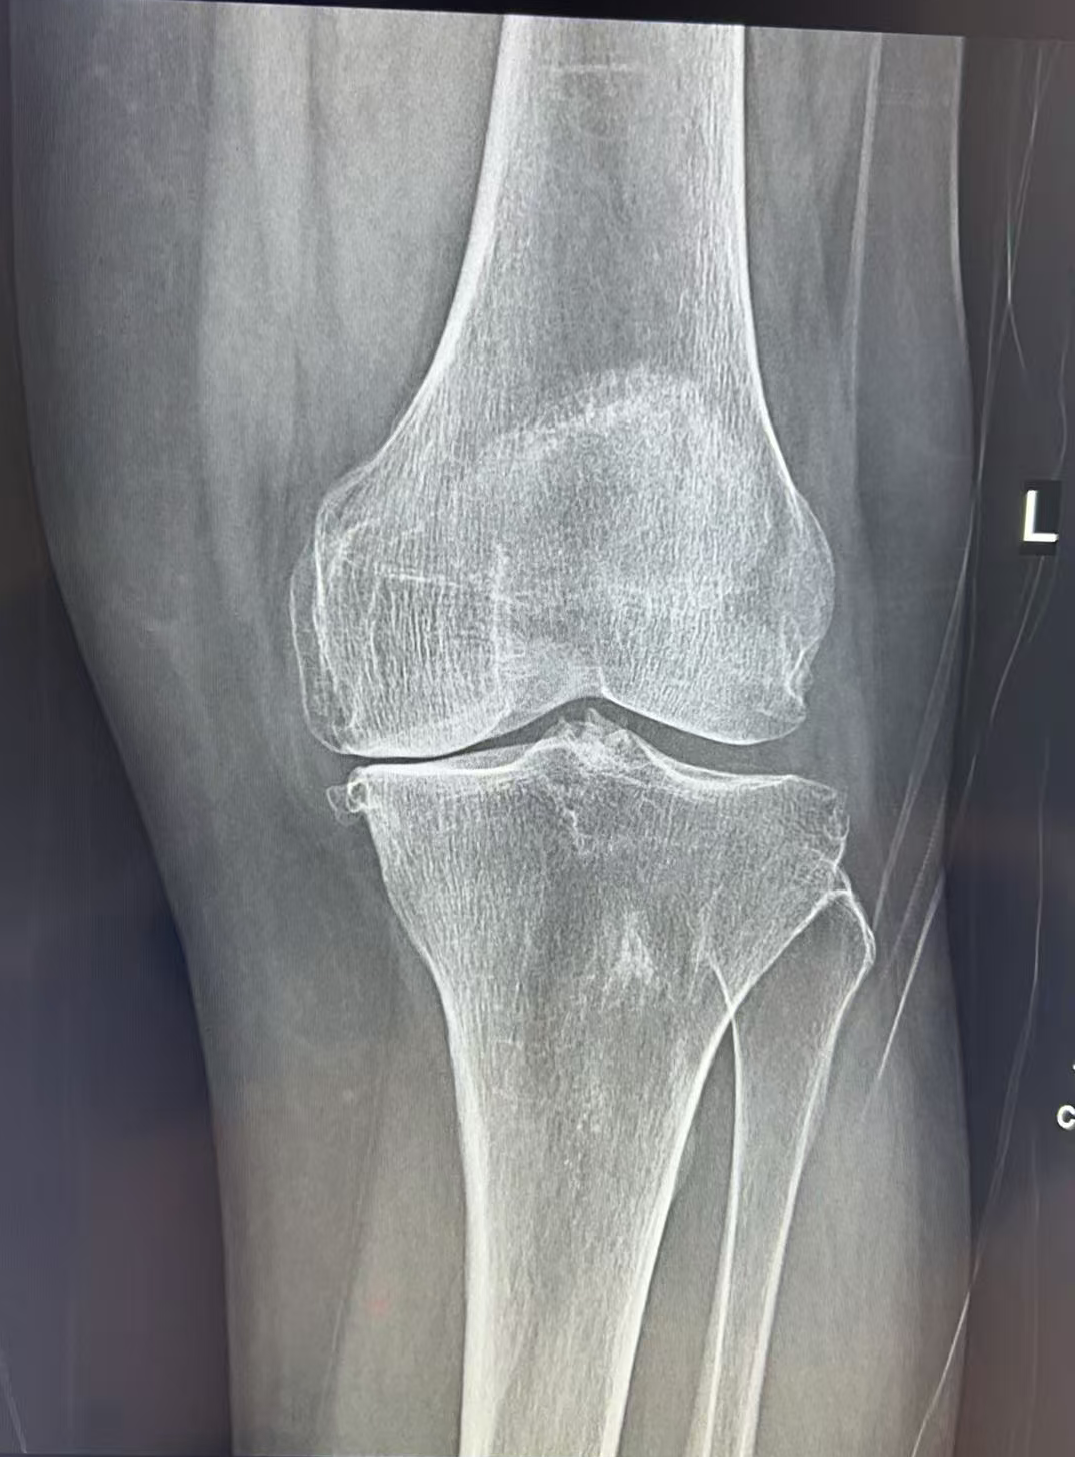

接诊她的是王歆峰主任,王主任耐心地听王阿婆讲了自己的情况,又仔细给她做了查体,还安排了详细的检查。最后确诊,王阿婆得的是“左膝关节骨性关节炎”。

经过仔细评估,王歆峰主任决定给王阿婆做“左膝内侧单髁表面置换术”!这就是保膝治疗的一种,简单说,就是只修复膝盖磨损的那一部分,不用把整个膝盖关节换掉,创伤小、恢复快,还能保留膝盖原本的功能。

像王阿婆这样的中老年人,膝盖疼反反复复,确诊为膝关节骨性关节炎,而且磨损主要集中在膝盖的一侧,没有严重的畸形,大多都适合保膝治疗。当然,具体能不能做,还得医生经过详细检查和评估后才能确定。